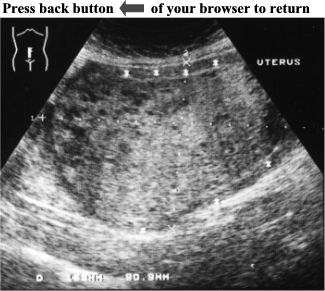

Pelvic ultrasound of this female patient revealed an enlarged uterus (15.8cm X 9.1cm). There was a large, non-homogeneous, solid mass  filling whole uterus. Several, small anechoic structures were scattered all over the mass where it was surrounded by normal myometrium (see asterisks).

CASE05-01jpg.jpg (24939 bytes)

click the picture to enlarge

Complete Hydatidiform Mole